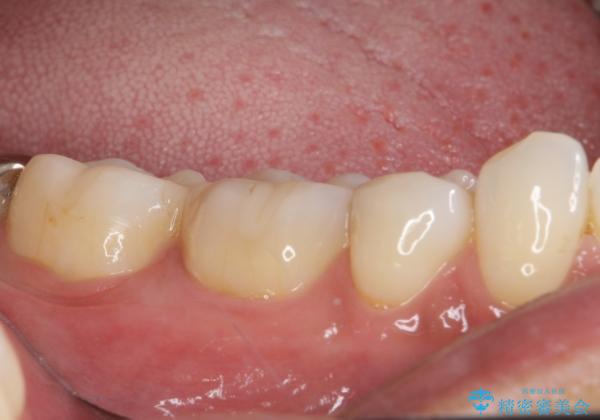

話をする度に相手の視線が銀歯に注がれている気がしているとのことでしたが、目立つ銀歯を自然な色合いに仕上げることができ、患者様には大変満足していただきました。